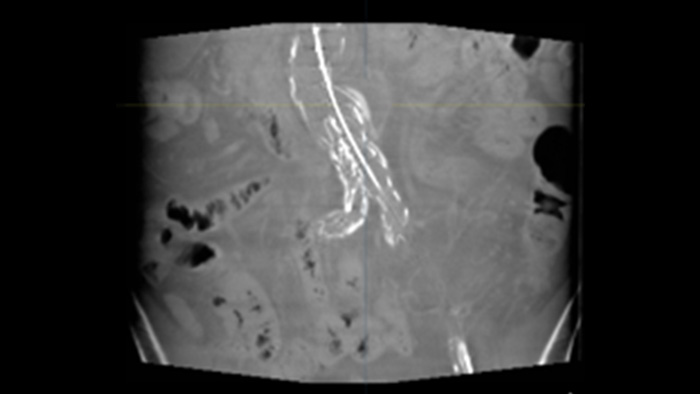

L'échographie intravasculaire (IVUS) est une technologie d'imagerie par cathéter qui permet aux médecins de visualiser les vaisseaux sanguins de l'intérieur vers l'extérieur pour faciliter l'évaluation de la présence et de l'étendue de la maladie. L'IVUS aide à décider, guider et confirmer le traitement interventionnel approprié pour chaque patient.

SmartCT Soft Tissue est une technique d'acquisition de rayons X qui génère une visualisation de type CT des tissus mous par rapport à d'autres structures pendant les procédures - le tout contrôlé par l'écran tactile de la table. Vous pouvez utiliser les images de type CT pour évaluer les tissus mous, la structure osseuse et le déploiement du stent.

Cette technique d'acquisition par rayons X permet de générer une visualisation complète en 3D haute résolution des vaisseaux cérébraux, cardiaques, abdominaux ou périphériques à partir d'un seul passage d'angiographie rotationnelle, le tout contrôlé par l'écran tactile de la table.

SmartCT Roadmap fournit une superposition d'images 3D en direct qui peut être segmentée pour mettre en évidence le vaisseau et les lésions ciblés, ce qui permet une navigation rapide du cathéter. Le SmartCT Roadmap superpose une reconstruction 3D de l'arbre vasculaire, des segments de vaisseaux ou des annotations avec des images fluo en direct.